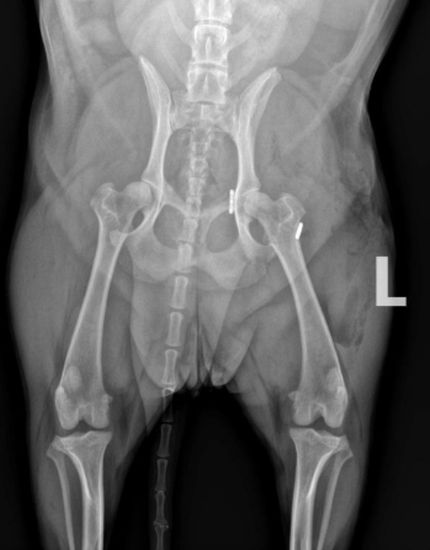

Dog with bilateral, staged double pelvic osteotomy (pre-operative and 8 weeks post)

Double pelvic osteotomy (DPO) and triple pelvic osteotomy (TPO) are very similar in concept to Juvenile Pubic Symphysiodesis (JPS). With DPO/TPO the pelvis is cut (with a saw) so that the socket can be rotated over top of the ball portion of the joint to provide more coverage to the ball. Hence, the ball is prevented from sliding (partially) out of the joint. The difference between DPO/TPO and JPS is that with JPS this coverage of the ball is increased gradually over time, and with double pelvic osteotomy (DPO) and triple pelvic osteotomy (TPO) this is achieved immediately.

Dogs that are candidates for double pelvic osteotomy (DPO) and triple pelvic osteotomy (TPO) are typically young, about 5-11 months of age (approximately). Really, a dog is a candidate if the hips are well formed, and there is no osteoarthritic change yet, but the hips are loose (lax) and we know those dogs are at risk of developing osteoarthritis later in life.

Double and triple pelvic osteotomy are named as such because the pelvis is cut (osteotomized) either in 3 places (triple) or two places (double) in order to rotate that socket (one socket) over the ball. Triple pelvic osteotomy is the older way of doing it, double pelvic osteotomy has been used since 2006. In Dr. Franklin’s opinion, the evidence and experience show this is a really good hip dysplasia surgery for dogs that are good candidates, but the challenge is appropriately identifying patients that are good candidates. Many dogs already have osteoarthritic change and cartilage wear of the hips by the time they are diagnosed and hence are not candidates.